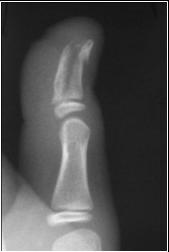

Longitudinal fracture

n Occurs along long axis

of bone